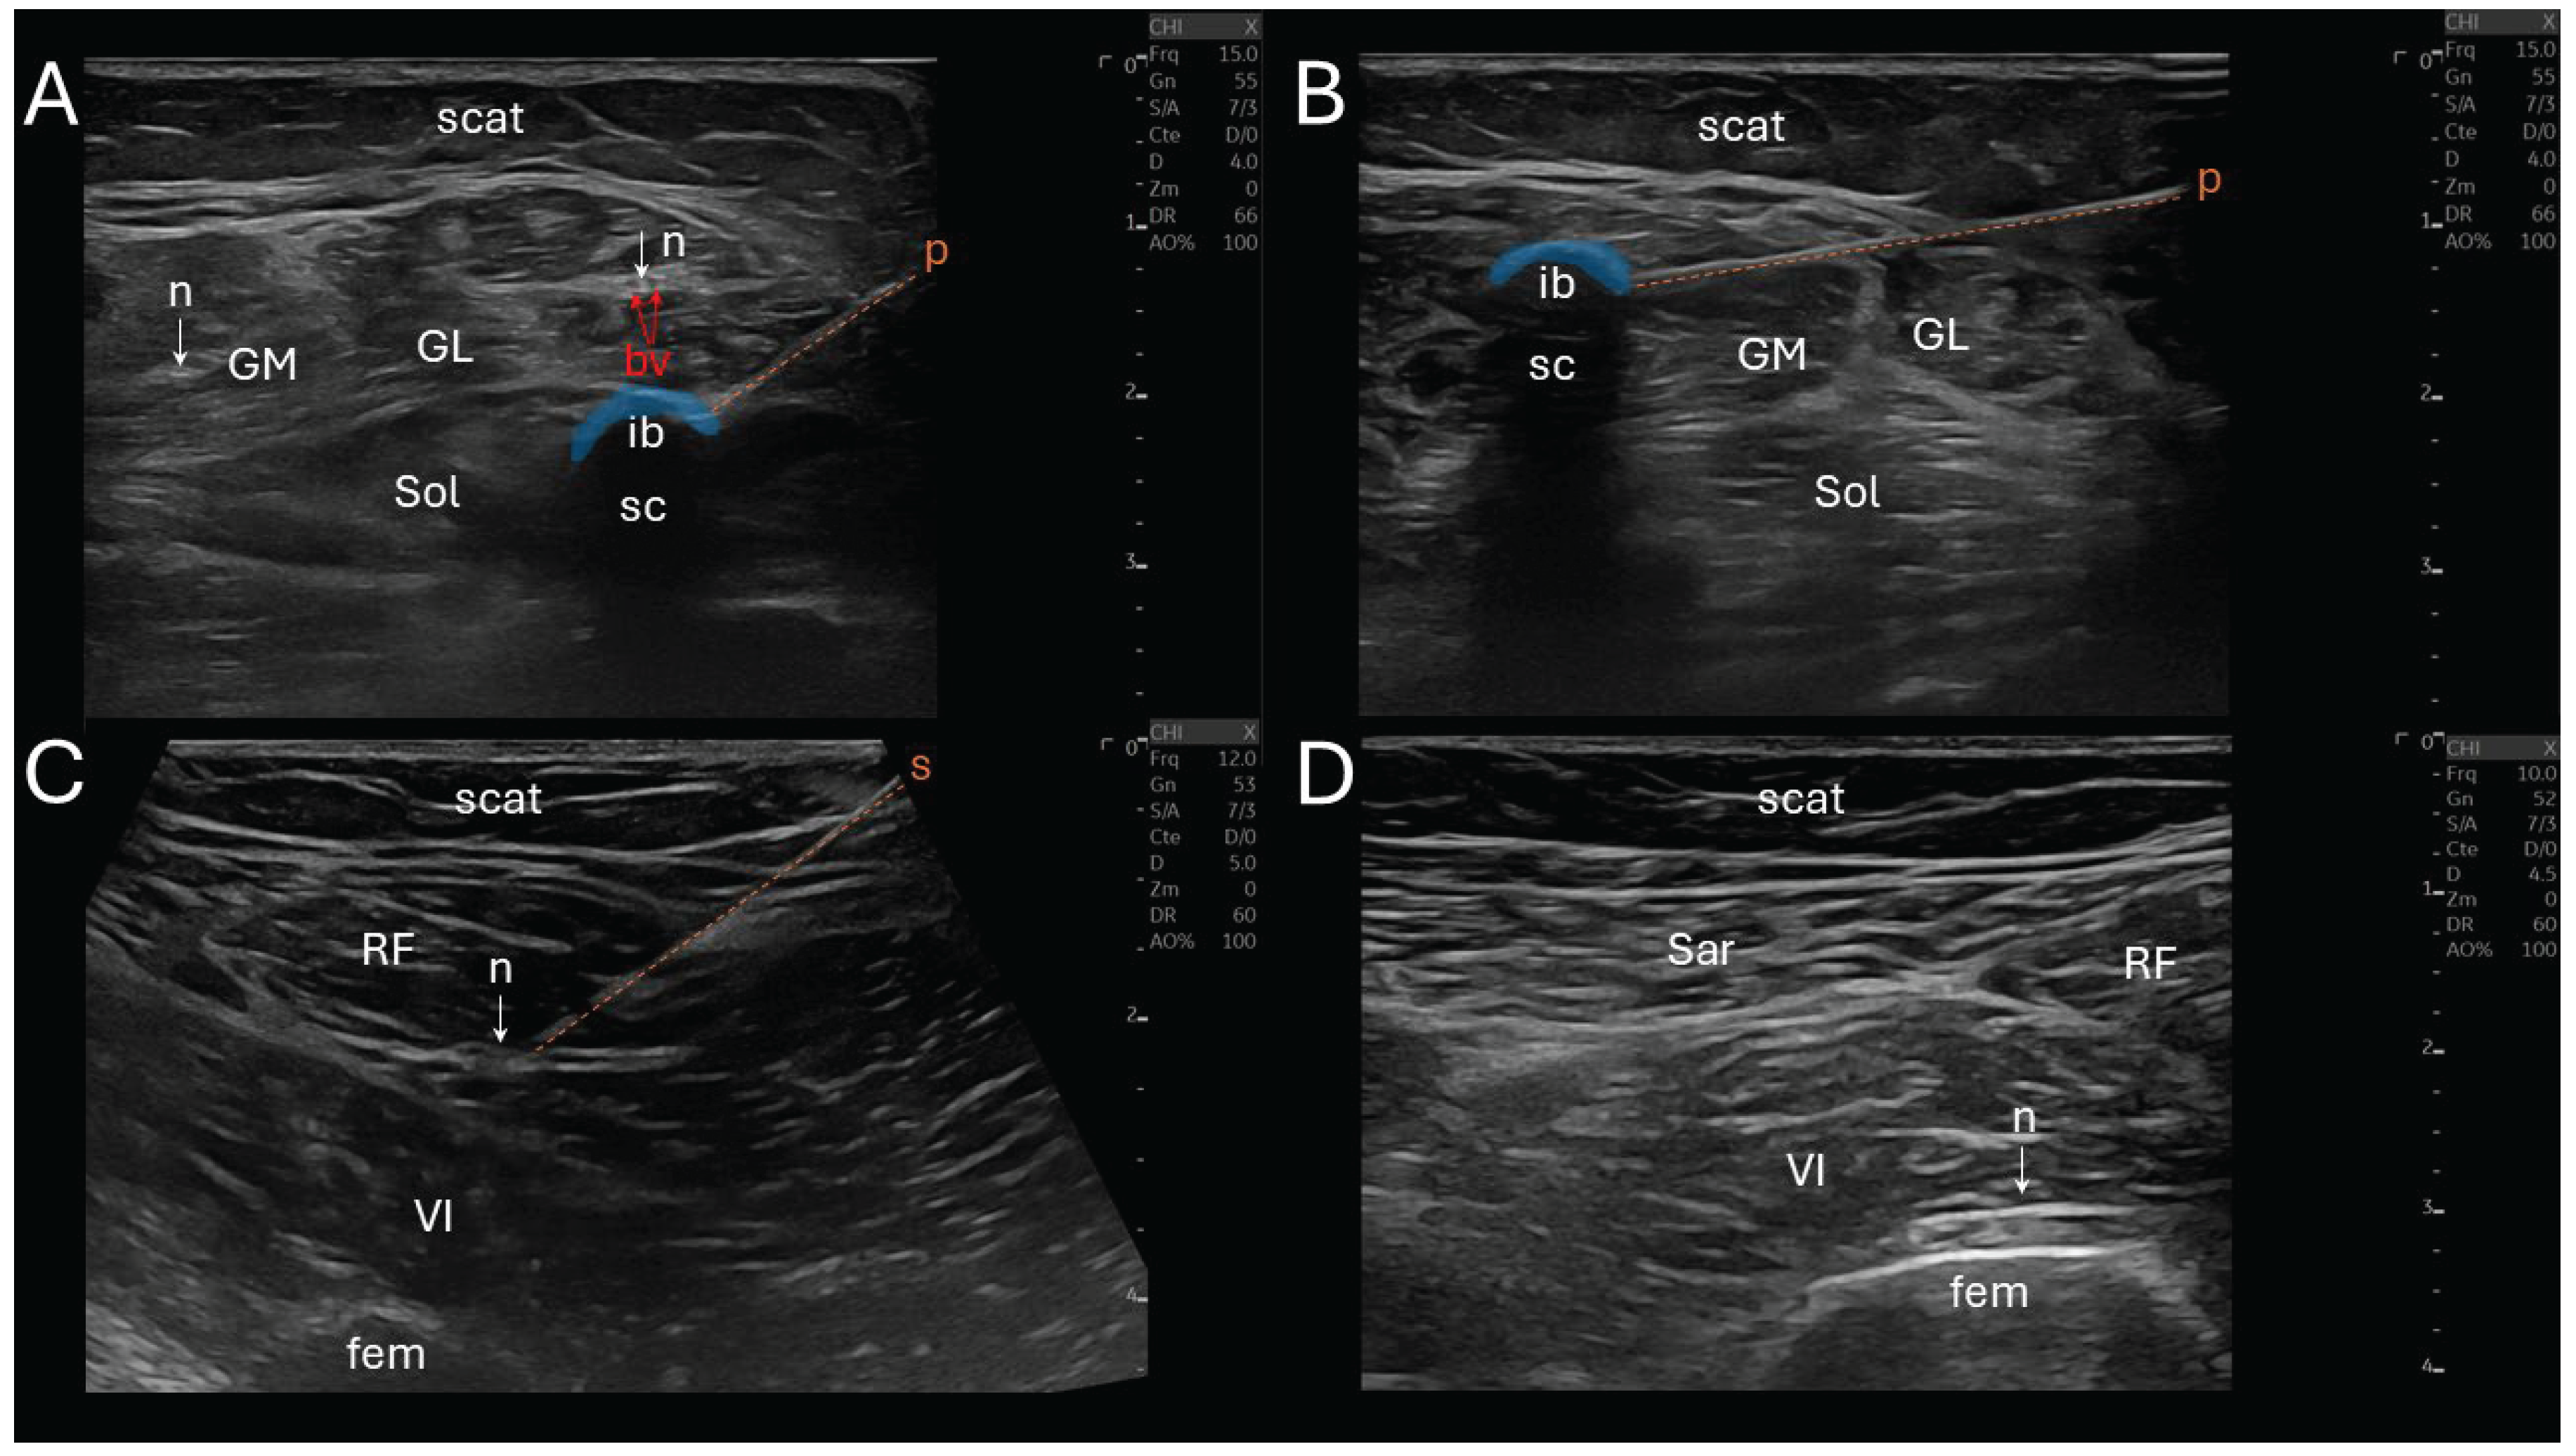

Figure 2. Ultrasound-guided CNL of tibial and femoral motor branches. (A) Transverse view showing the cryoprobe (p) freezing phase of one of the soleus (Sol) motor branch with the hypoechoic ice ball (ib) and a posterior shadow cone (sc) at the probe tip, and adjacent gastrocnemii medialis (GM) and lateralis (GL) respective nerves (n); (B) view of the freezing phase of one of the GM motor branch with ib and sc; (C) view of the stimulation needle (s) on one of the rectus femoris (RF) motor branch (n); (D) view of one of the vastus intermedius (VI) motor branch (n), and adjacent sartorius (Sar) and RF. bv = blood vessels, fem = femur, scat = subcutaneous adipose tissue.

CNL was performed using a N₂O-based system (Metrum Cryoflex, Warsaw, Poland) delivering cryogenic temperatures through a 14G percutaneous cryoprobe (Figure 2). The target motor nerve was cooled to approximately –30 °C to –40 °C to induce a controlled, reversible axonotmesis. All CNL procedures were conducted under sterile conditions, without sedation or general anesthesia, and under real-time ultrasound guidance using a linear 10-15 MHz probe (Logiq E10, General Electric, Boston, MA, USA).

The seven procedural steps of CNL (total duration ≈ 1 hour) were the following: (i) a sonographic landmarking in a transverse view, (ii) the introduction of an insulated stimulation needle (22G, 10 cm) via an in-plane technique, directing it towards the nerve trajectory, while avoiding vascular structures, (iii) a nerve stimulation initiated at 2 mA, gradually reduced to 0.5 mA to ensure close proximity to the motor fascicles (muscle contraction remains visible), (iv) needle-to-cryoprobe exchange, (v) a reconfirmation neurostimulation twitch via the cryoprobe prior to freezing, (vi) the CNL phase (first cycle: 2 minutes continuous freezing, thawing: 45 seconds, second cycle: another 2 minutes freezing) creating an ellipsoidal anechoic ice ball and its posterior acoustic shadow cone at the tip of the cryoprobe, and (vii) a post-lesion stimulation was performed to confirm temporary denervation (absence of evoked muscle contraction at 1 mA). If the nerve still responded to this stimulation, a supplemental freezing of 2 minutes was applied.

The stimulation of the soleus was performed proximally, 2-3 cm distal to the popliteal fossa, in two points, medially and laterally close to the tibial nerve. The gastrocnemius medialis stimulation was performed slightly more proximally, intramuscularly. The rectus femoris and vastus intermedius stimulations were also performed proximally, distal to the inguinal ligament, laterally close to the femoral nerve, and the vastus intermedius stimulation required a deeper insertion.